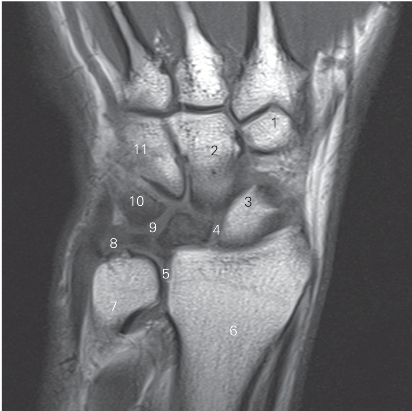

图4-55 经下尺桡关节的冠状断层MR T1加权图像

1 小多角骨 trapezoid bone 2 头状骨 capitate bone

3 舟骨 scaphoid bone 4 舟月韧带 scapholunate ligament

5 下尺桡关节 distal radioulnar joint 6 桡骨 radius

7 尺骨 ulna

8 三角纤维软骨 triangular fibrocartilage

9 月三角韧带 lunatotriquetral ligament 10 三角骨 triquetral bone

11 钩骨 hamate bone